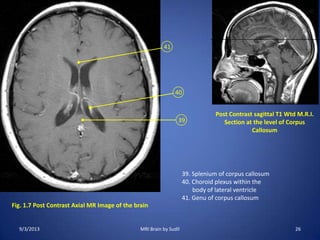

Fig. 1.7 Post Contrast Axial MR Image of the brain

39

40

41

Post Contrast sagittal T1 Wtd M.R.I.

Section at the level of Corpus

Callosum

39. Splenium of corpus callosum

40. Choroid plexus within the

body of lateral ventricle

41. Genu of corpus callosum

9/3/2013 26MRI Brain by Sudil